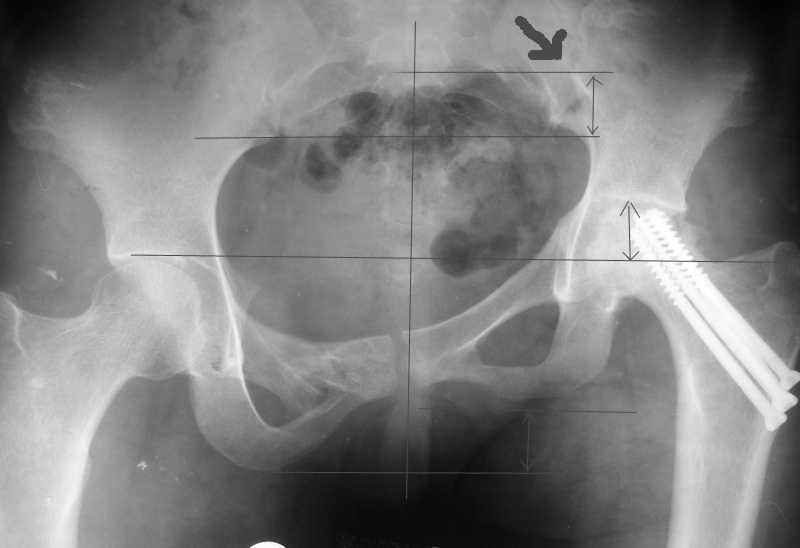

[Ortho] AVN of femoral head and fracture of the pelvis.

Привет, Макс. Не торопись, посмотри внимательно на истинную картину. Толстая стрелка указывает на нижний край смещенного кп сочленения.

Поэтому считаю, что Принять какое-либо решение без кт и дополнительных проекций неразумно.